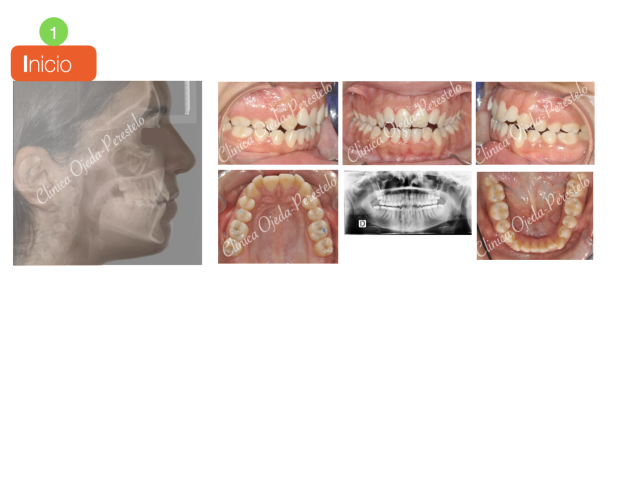

Mordida Cruzada Bilateral Casos de Éxito - Mordida Cruzada - Niños

Clase III esquelética en dentición mixta Casos de Éxito - Niños

Clase III esquelética en dentición definitiva Casos de Éxito - Niños